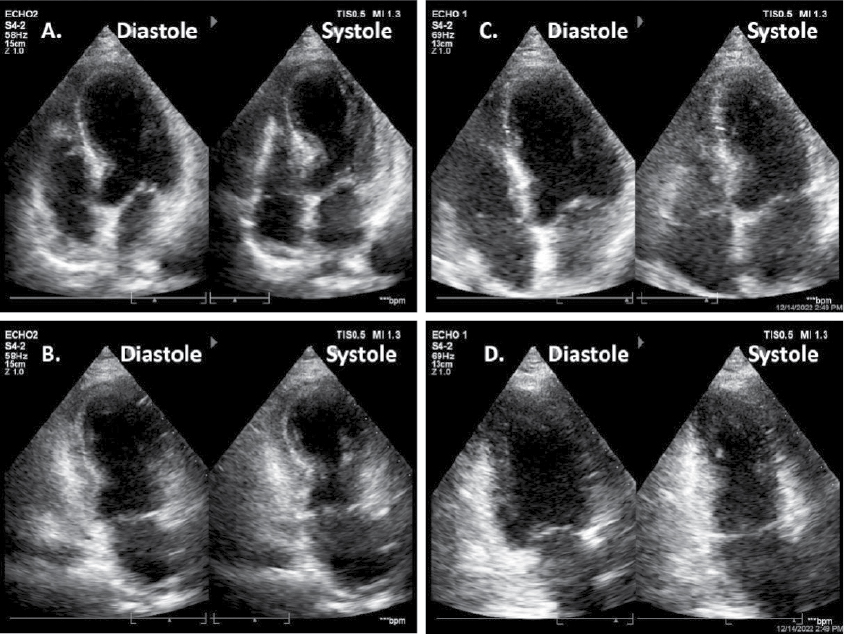

A 75-year-old diabetic female presented to the emergency department with complaints of acute onset shortness of breath and chest heaviness. She did not complain of any other abdominal or chest symptoms. Other than emotional frailty owing to social loneliness, her personal and family history were unremarkable. She was living with normal coronaries evaluated 4-year back for chest pain with ST-segment elevation on electrocardiogram (ECG). Follow-up ECG (Fig. 1A) and transthoracic echocardiography (TTE) over last few years were unremarkable. On general physical examination, patient was seen to be anxious. The heart rhythm was regular with a rate of 108 beats/min; the blood pressure was 130/80 mmHg and respiration was thoraco-abdominal with a rate of 24 breaths/min. Findings from review of the systems, other than as reported above were normal. A 12-lead surface ECG showed sinus tachycardia and ST-segment coving with T-wave inversion in precordial and limb leads (Fig. 1B). Qualitative cardiac troponin T was negative and routine biochemical analysis including complete blood count, renal and liver function tests were unremarkable. TTE revealed severe left ventricular systolic dysfunction (ejection fraction about 35% by Simpson) with marked regional wall motion abnormalities in the mid anterior, mid-septal, mid inferior and apical segments of the left ventricle (Fig. 2A and 2B). The patient was immediately shifted to the catheterization laboratory, where coronary angiography was done. Angiography revealed normal coronary arteries with mild plaquing of major epicardial vessels (Fig. 3).

Figure 2. Echocardiogram in apical 4 chamber and apical 2 chamber views during acute event (A & B) showing apical akinesis and basal hyperkinesis leading to characteristic appearance of apical ballooning or Japanese Takotsubo (octopus pot) in systolic frame. Follow-up echocardiogram in same views after 4 weeks of follow-up (C & D) showing normalization of wall motion abnormalities.

The patient was treated with beta-blockers, ACE inhibitors, dual antiplatelets, statins, diuretics and antidepressants. She was discharged in a stable condition after 3 days without any complications. She was re-evaluated after 4 weeks. At the follow-up visit, all her symptoms had disappeared. ECG showed repolarization abnormalities in the form of T-wave inversion consistent for previous event (Fig. 1C). Echocardiography showed normalization of the left ventricular systolic function (ejection fraction about 60% by Simpson) with no residual wall motion abnormality (Fig. 2C and 2D).